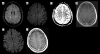

We report the first case of combined retinal and CNS varicella zoster-associated vasculitis in a 49-year-old patient with multiple sclerosis who had been treated with natalizumab. He presented with a progressive bilateral visual loss. The diagnosis of a vasculitis was based on the fundoscopic examination and MRI findings. We confirmed the varicella zoster virus (VZV) infection of the CNS by PCR and increased intrathecal antibody indices in the cerebrospinal fluid. The patient was stabilized with antiviral treatment, methylprednisolone, plasmapheresis and cycophosphamide. Natalizumab was discontinued. This case illustrates the neuroimmunological and neuroinfectiological consequences of treatments with biologicals that influence the immune system.